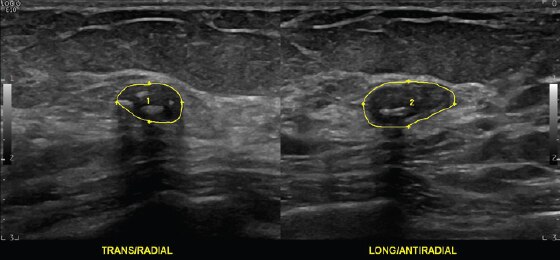

Benign Breast Mass with Multiple Calcifications, ML6-15-D

The LOGIQ E10 system helps you make a real difference in the lives of patients with breast disease.